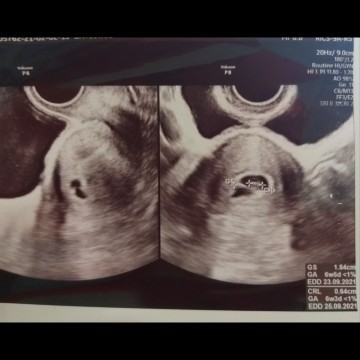

Ukuran janin dan detak jantung

Hasil usg kmren, kata dokter ukuran tidak sesuai dgn usia kehamilan 9 minggu kata dokter janinnya tdk berkembang, terlalu kecil dan blum ada detak jantung. Dianjurkan usg 2 mnggu lagi. adakah bundah bunda mengalami hal yg sama dengan saya? #seriusnanya #firstbaby